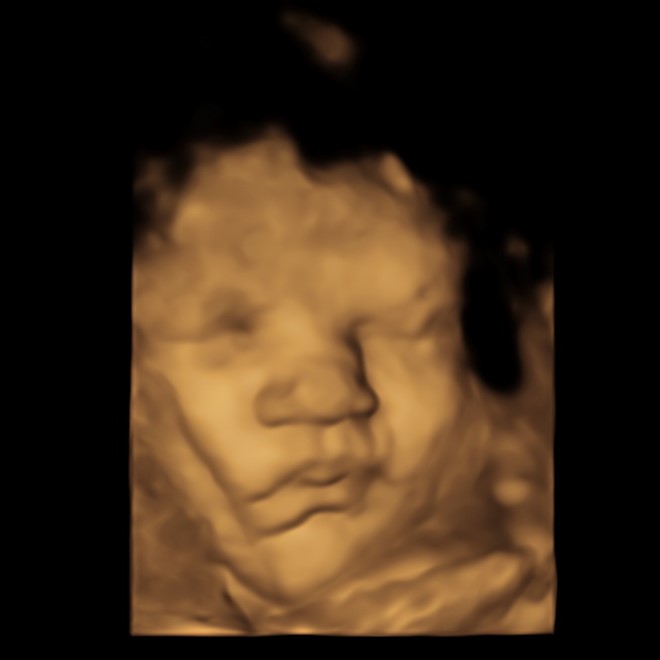

A 3D scan has the dimension of depth, giving superior and more realistic character to the image and enabling parents to see what their baby looks like. Facial expressions can sometimes be captured such as a smile or a frown. 4D enables you to see 3D imaging live. You can watch a live video of your baby from within the womb, watching his or her movements and expressions. The scan lasts 20 - 30 minutes and includes images plus a personalised video recording of your baby that you can download to your device via a link we provide.